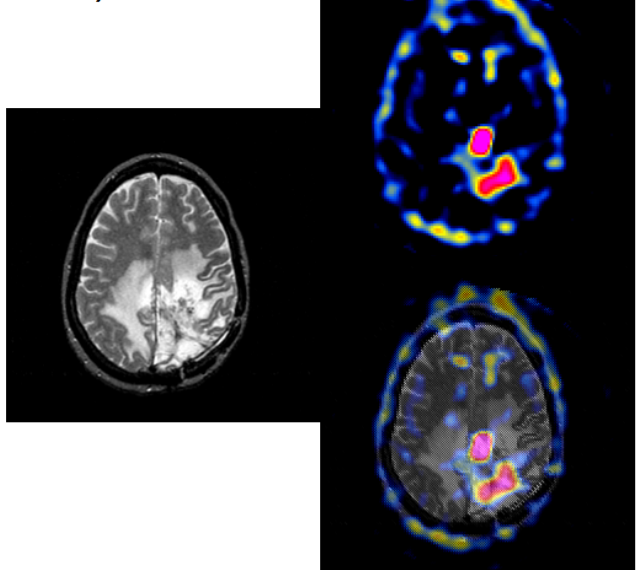

How can radioligands be used to visualise the brain (e.g. BBB breakdown or tumours)?

[EXTRA?]

What do these scans show?

(Pathology on left scan, right scan is an age-matched control)